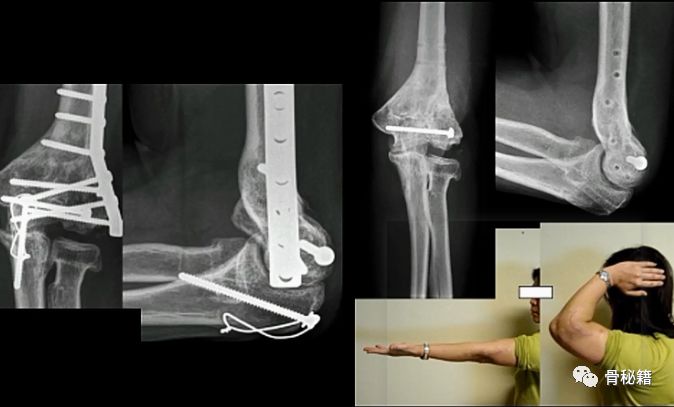

看看这些失败的case,肱骨远端不简单!

【骨折的复位和固定】

早期的AO技术

AO最早是90-90度钢板的派系,与平型钢板打的火热,后来没打过

1.钢板的形态没有特殊特定的,需要塑性预弯尤其在控制远端的骨折块的时候,钢板和螺钉的角度都必须十分讲究2. 对于滑车的固定只能应用最远端的拉力螺钉,与钢板不能连接3.这种固定在肱骨髁之间无法完成较好的骨折块之前的加压固定

所以对于这样固定的患者就面临一个问题,如果敢早期锻炼,就可能愈合不良,如果石膏固定时间长的话,肘关节就会僵硬

基于应用AO技术的话,固定要点1.一定要将钢板尽量往远端放,把远端骨块固定好2.髁间的固定一定要坚强,加压!3.尽量的坚强固定4.固定基础下早期功能锻炼